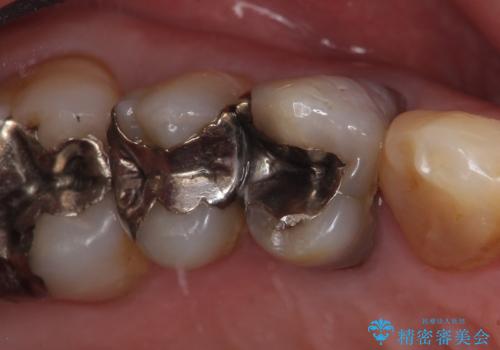

- 右上4番目の歯が黒くなっているのが気になるといらっしゃった方の症例です。

再根管治療後、オールセラミッククラウンによる補綴を行いました。

右上5も虫歯があったためオールセラミッククラウンによる補綴を行っております。